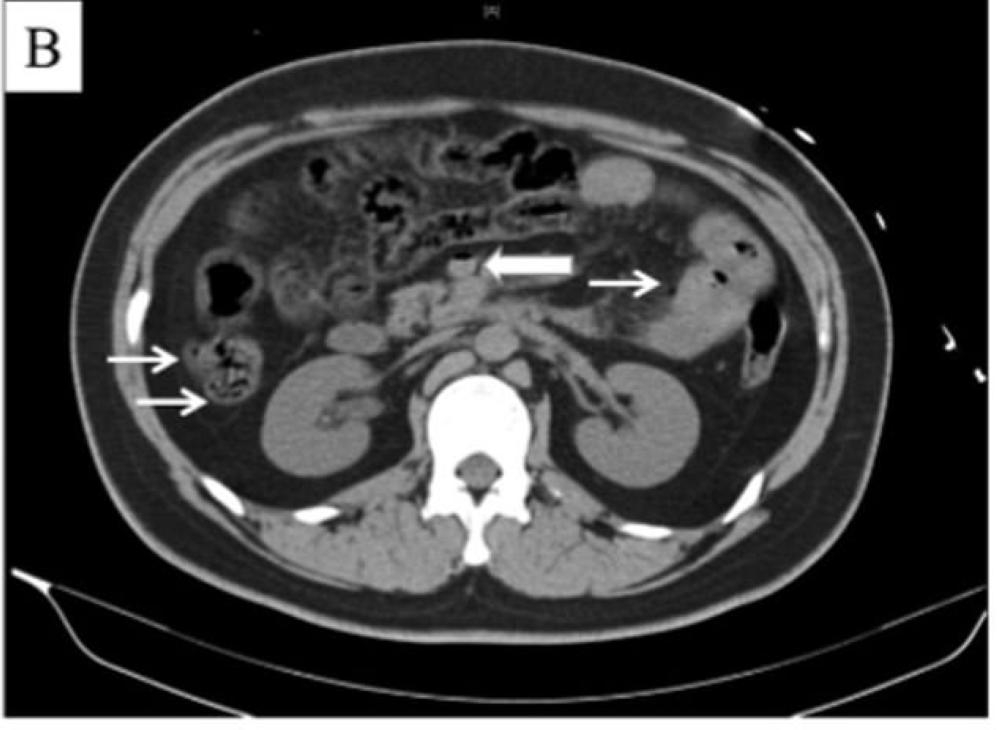

وكشفت عمليات المسح عن إصابته بنقص تروية الكبد، المعروف أيضًا باسم «صدمة الكبد»، وهو نوع من الأمراض الناجمة عن انخفاض إمداد العضو بالأكسجين، الذي يعتقد الأطباء أنه مرتبط بوجود غاز في الوريد البابي.